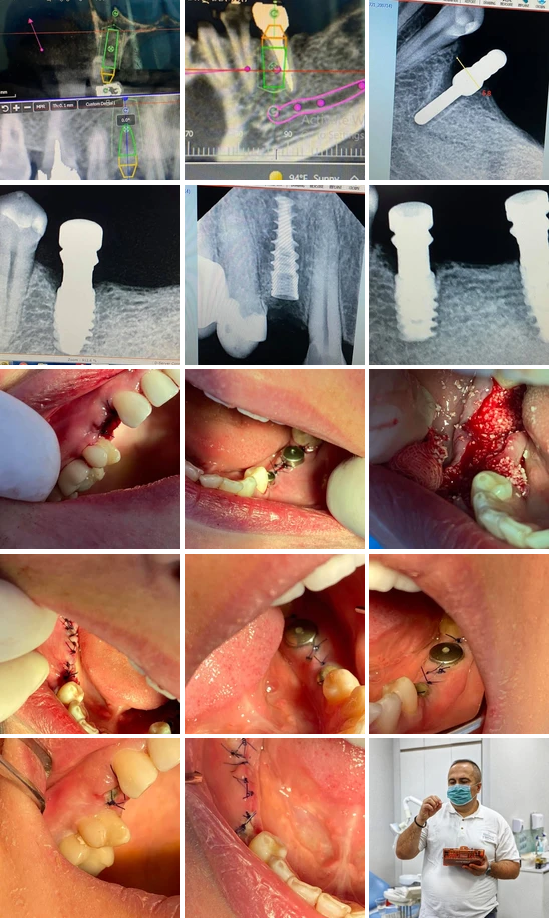

Установка имплантата на верхней челюсти, удаление с немедленной имплантацией плюс удаление и аугментация нижней челюсти. Размер имплантата P7D SGS 3,75-11,5 мм. Имплантат уставлен в область 15 зуба, с торком 40 Нсм. 35 зуб депульпирован, извлечен и проведена немедленная имплантация. Проблема здесь заключалась в расположении нижнечелюстного нерва. Расстояние от верхушки альвеолярного гребня до апикальной части корня зуба составляет 10 мм, а до нерва – 11 мм. Установлен P7D 5-8 мм, с торком 40 Нсм. Дополнительно установлен P7D 4,2-10 мм в область 37 зуба. Также были удалены 45-47 зубы и проведена аугментация костным трансплантатом. Снимки были сделаны на 4-й день после операции.

Хирургическую операцию провел грузинский стоматолог, ортопед и имплантолог Михаил Церетели.